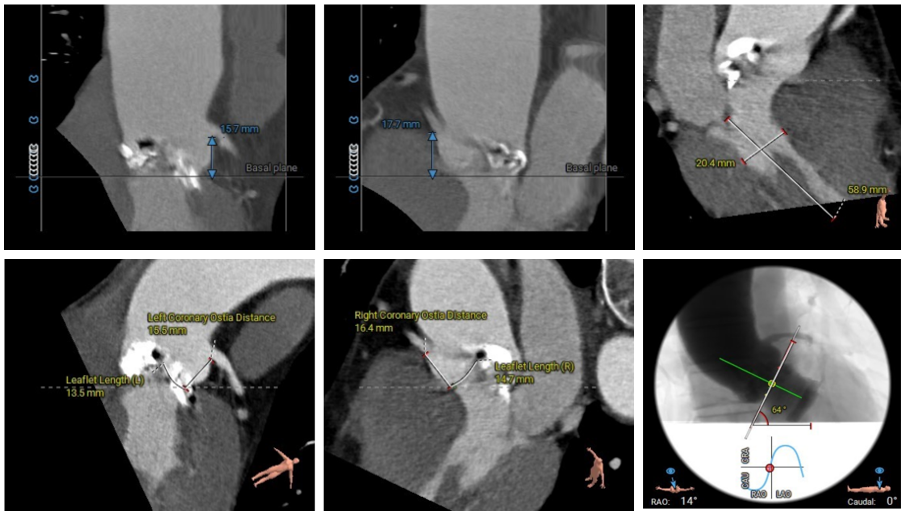

术前CT评估

●Type1型二叶式主动脉瓣,L-R窦融合嵴,瓣叶增厚伴重度钙化,钙化延续至左室流出道;左、无冠窦瓣叶钙化较重;LVOT 呈收口形态;

●左右冠脉开口高度尚可,切线位测量未见冗长瓣叶;冠脉未见钙化斑块;

●瓦氏窦、窦管交界内径正常,升主动脉扩张;

●瓣环平面与水平夹角为64°,横位心,主动脉弓夹角、弓距尚可;

●入路血管情况良好。

主动脉根部测量

瓣上结构测量

冠脉阻挡风险、左室大小及横位心评估

外周血管入路评估